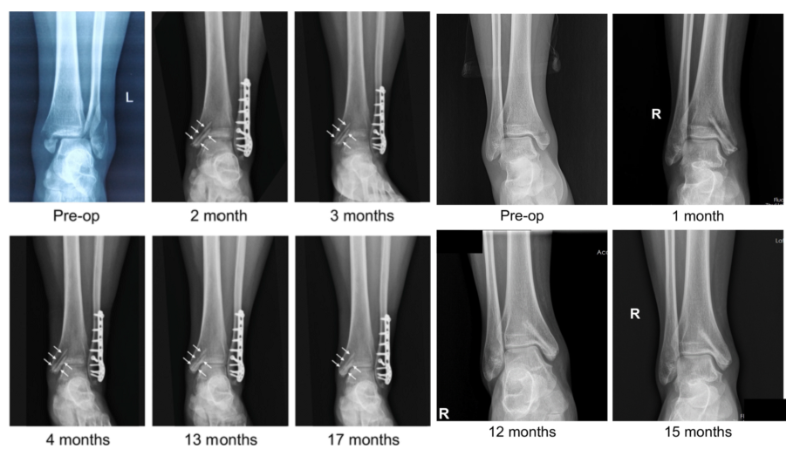

近日,國際骨科臨床轉(zhuǎn)化期刊《Journal of Orthopaedic Translation》在線發(fā)表了由上海交大戴尅戎院士、郝永強(qiáng)教授團(tuán)隊(duì)和丁文江院士、袁廣銀教授團(tuán)隊(duì)合作發(fā)表的可降解鎂合金骨釘1-2年的臨床試驗(yàn)觀察結(jié)果,所有患者術(shù)后內(nèi)踝骨折愈合,功能恢復(fù)。研究證實(shí)了可降解鎂合金螺釘治療內(nèi)踝骨折的臨床療效及其生物安全性,為全降解鎂合金植入物等高端醫(yī)療器械進(jìn)一步的臨床推廣應(yīng)用奠定了堅(jiān)實(shí)基礎(chǔ),相關(guān)成果以“Effectiveness and safety of biodegradable Mg-Nd-Zn-Zr alloy screws for the treatment of medial malleolar fractures”為題在線發(fā)表于Journal of Orthopaedic Translation,27 (2021) 96–100。這是國內(nèi)首個可降解醫(yī)用鎂合金臨床試驗(yàn)的公開報道,也是國際首款含有功能涂層的可降解鎂合金骨釘?shù)呐R床試驗(yàn)結(jié)果的公開報道,具有里程碑意義。